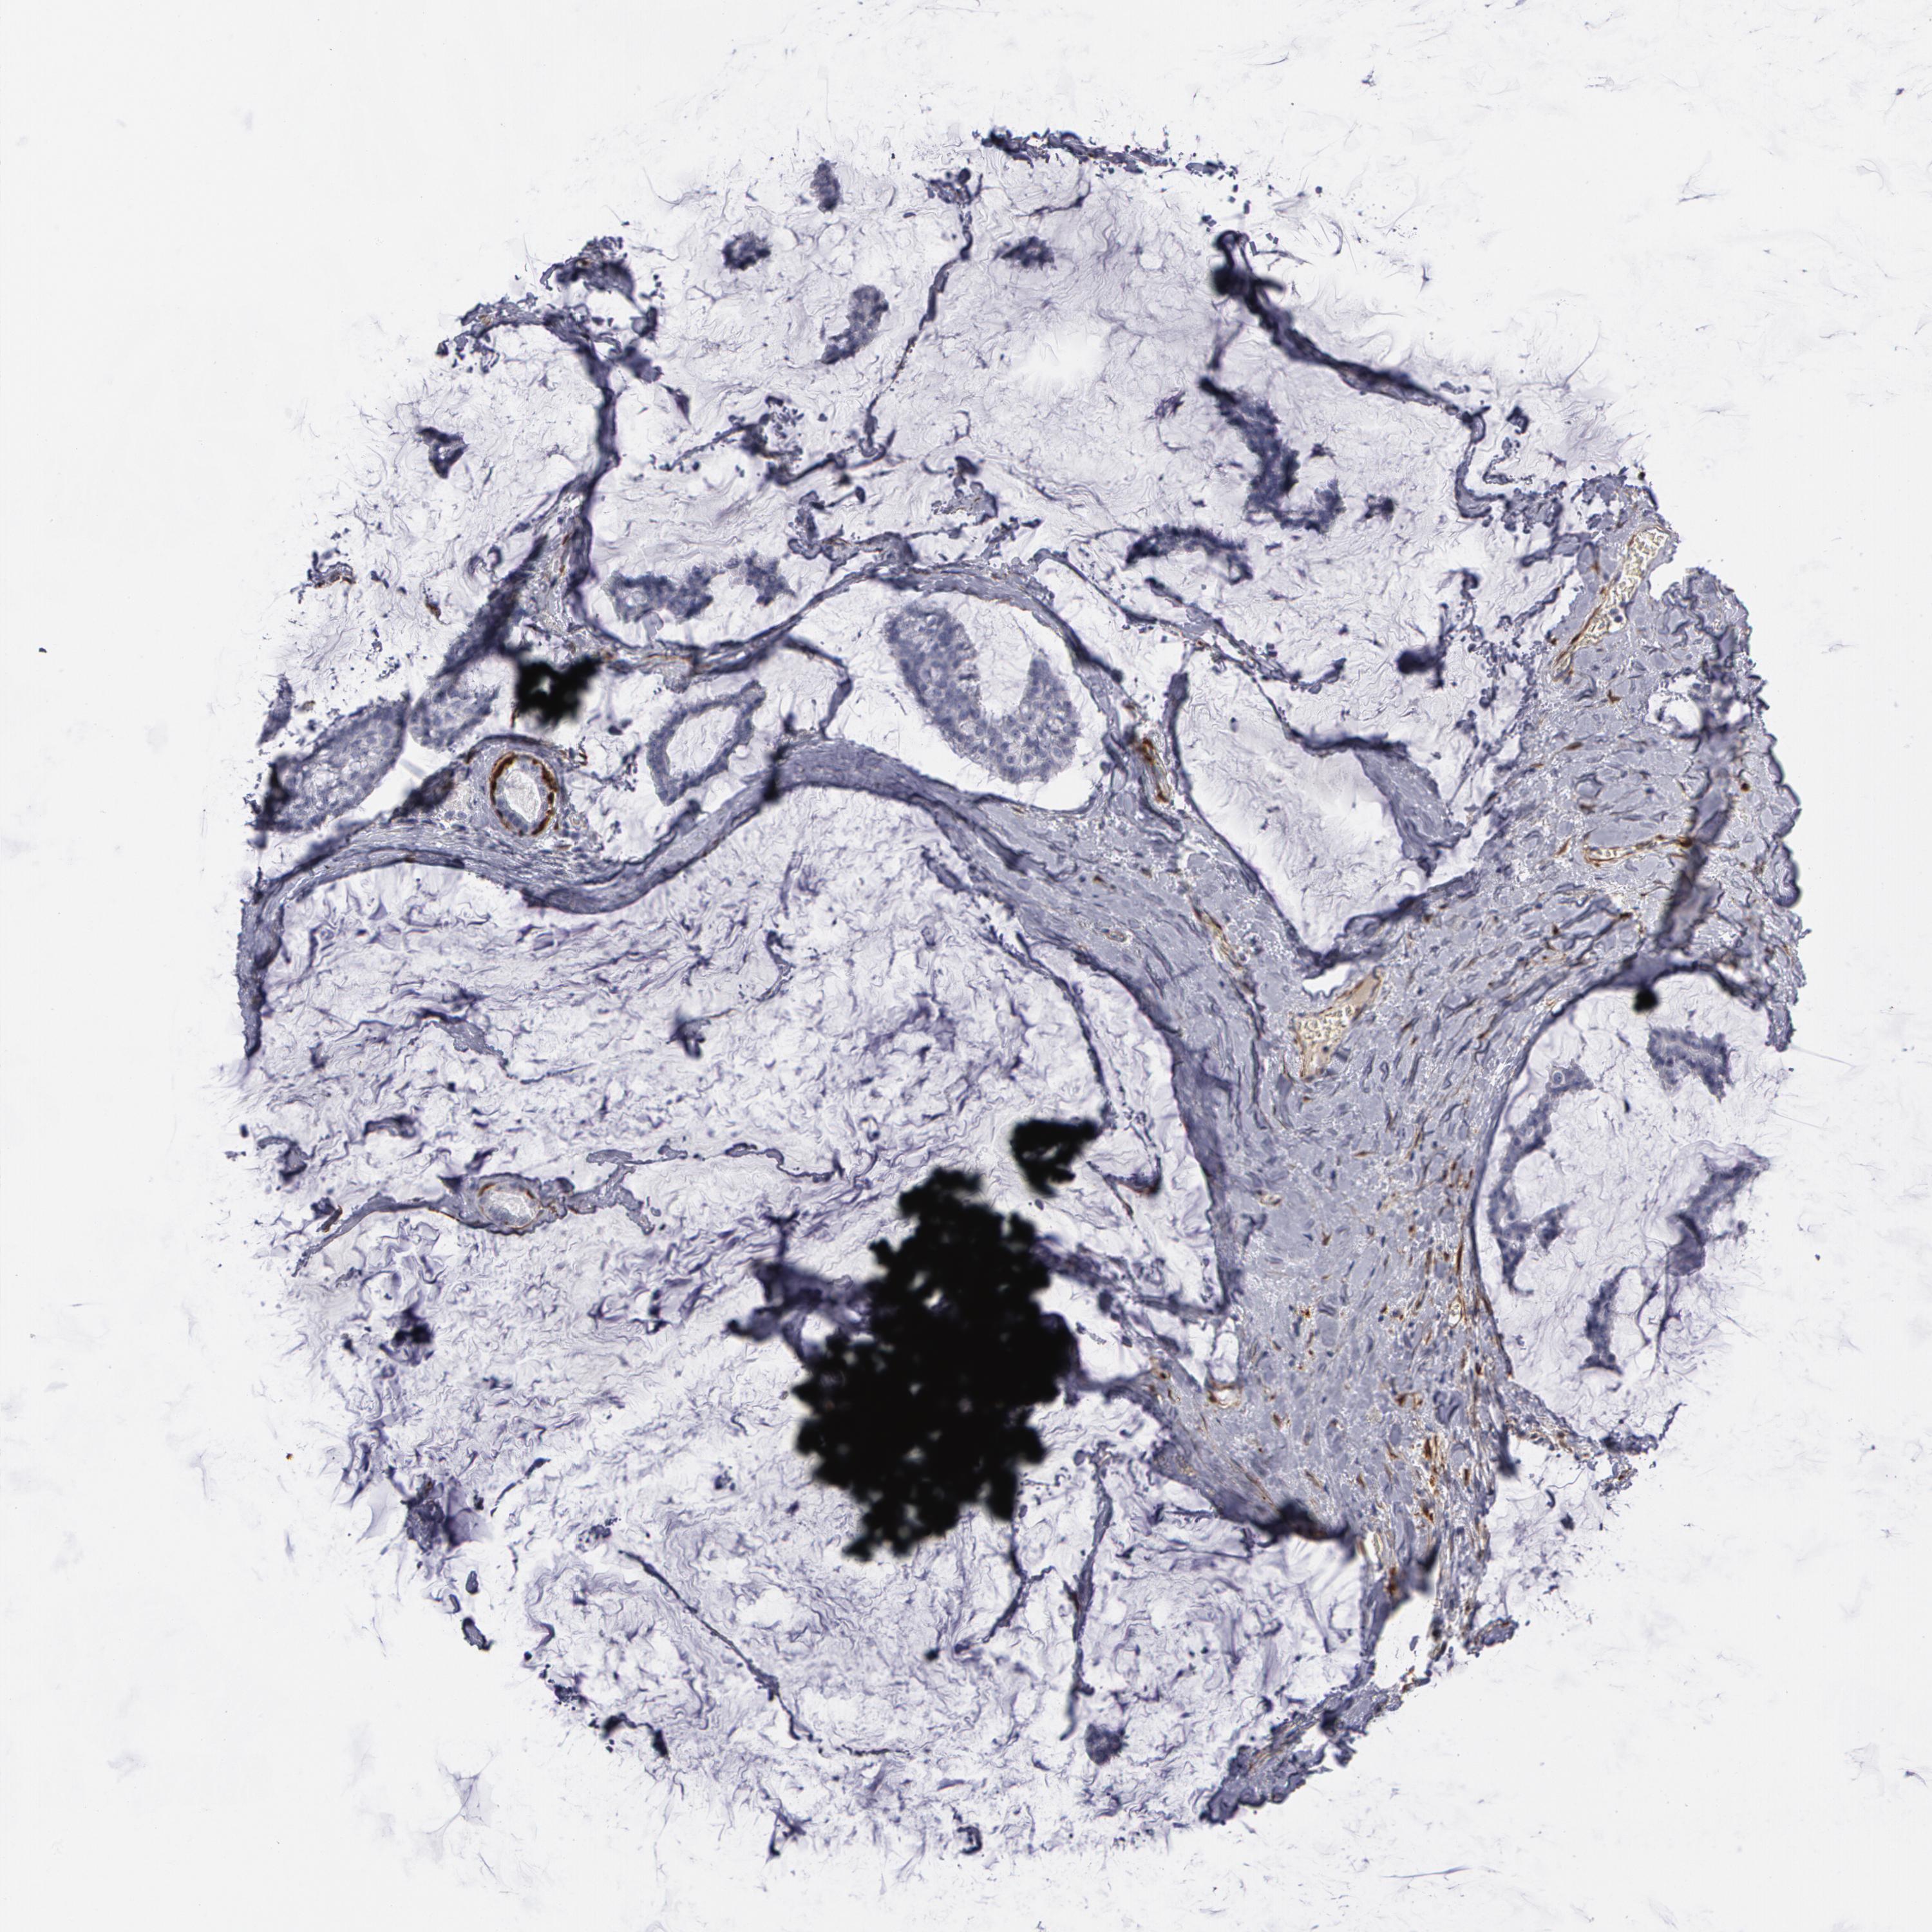

BRCA TCGA BRCA VALIDATION PROTEIN EXPRESSION